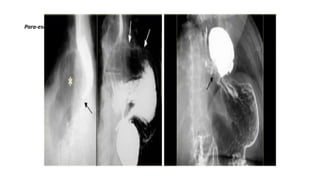

Para-esophageal hernia